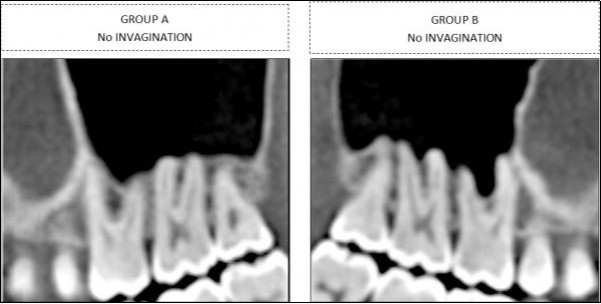

Findings for the molars were classified into two groups, depending upon whether sinus-floor invagination was present between the roots (Group B) or not (Group A) (Figure 2).

Figure 2.Classification in two different categories for molars , based on sinus invagination